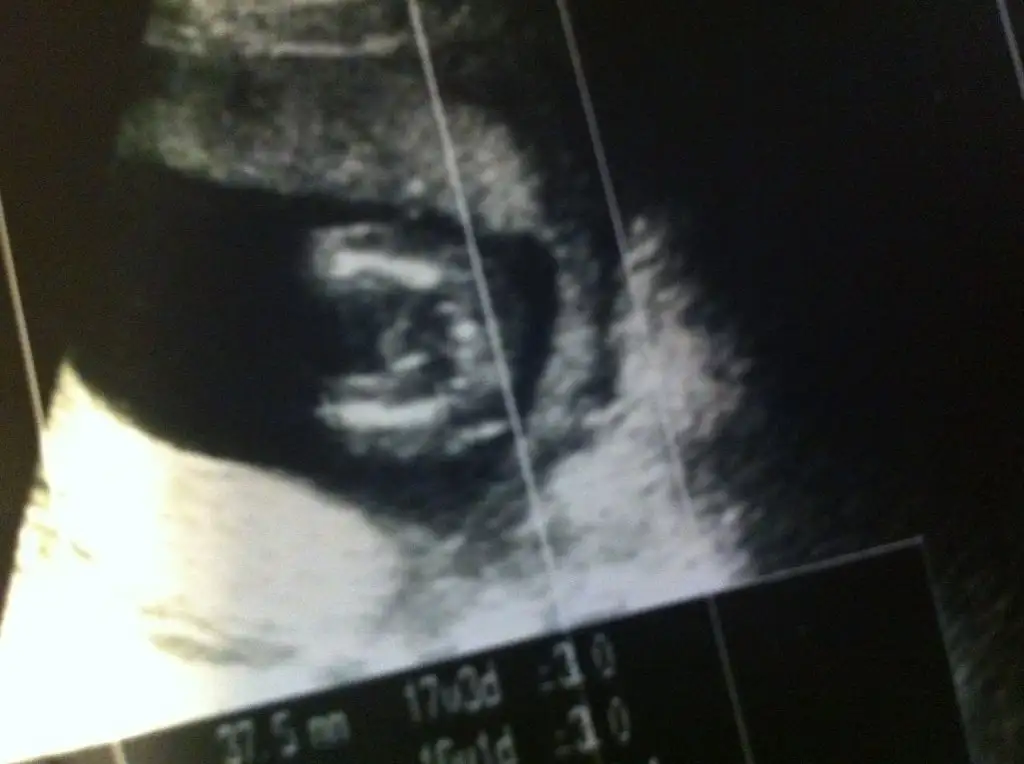

Kaç haftalık canım 17+3 diyor eğer doğruysa %99 erkek diyorum...Kızlar acile gittim gece göbek deliğim ağrıo die tesadüf eseri bu görüntüyü aldım ama dr cinsiyetini sölemedi tabi acil kalabalıktı sizce bizim bebiş nee tamda bacak arası açık Eki Görüntüle 1418093

Evet cnm 17 +4 teKaç haftalık canım 17+3 diyor eğer doğruysa %99 erkek diyorum...